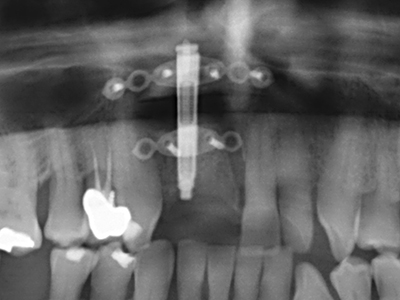

Както е показано в миналото, всяка костна хирургия представлява възможна индикация за пиезохирургия. По този начин, за препарацията на подвижни сегменти в остеогенеза (Фиг. 23-25) и остеотомия се използват специални накрайници, без да се застрашава снабдяването с кръв в кресталната зона, което е от съществено значение за успеха и на двете техники (Gonzalez-Garcia, Diniz-Freitas et al. 2008).